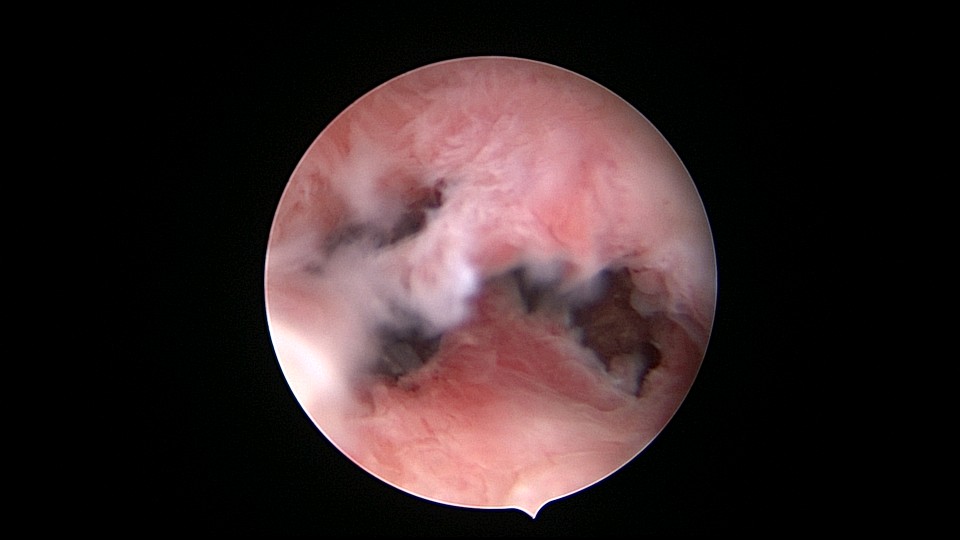

患者55岁,G4P1,顺产1次。安环16年,绝经5年,外院取环失败。子宫前位,宫颈萎缩,宫腔下段左后壁见假道,假道内见肌瘤结节突出,爱母环位置正常,宫腔左侧壁及前壁见占位质脆组织,表面有异常粗大血管。异物钳顺利取出节育环,占位组织病检为内膜样癌。取环造成的假道让病人因祸得福,提前发现了子宫内膜样癌,得以及时手术治疗。